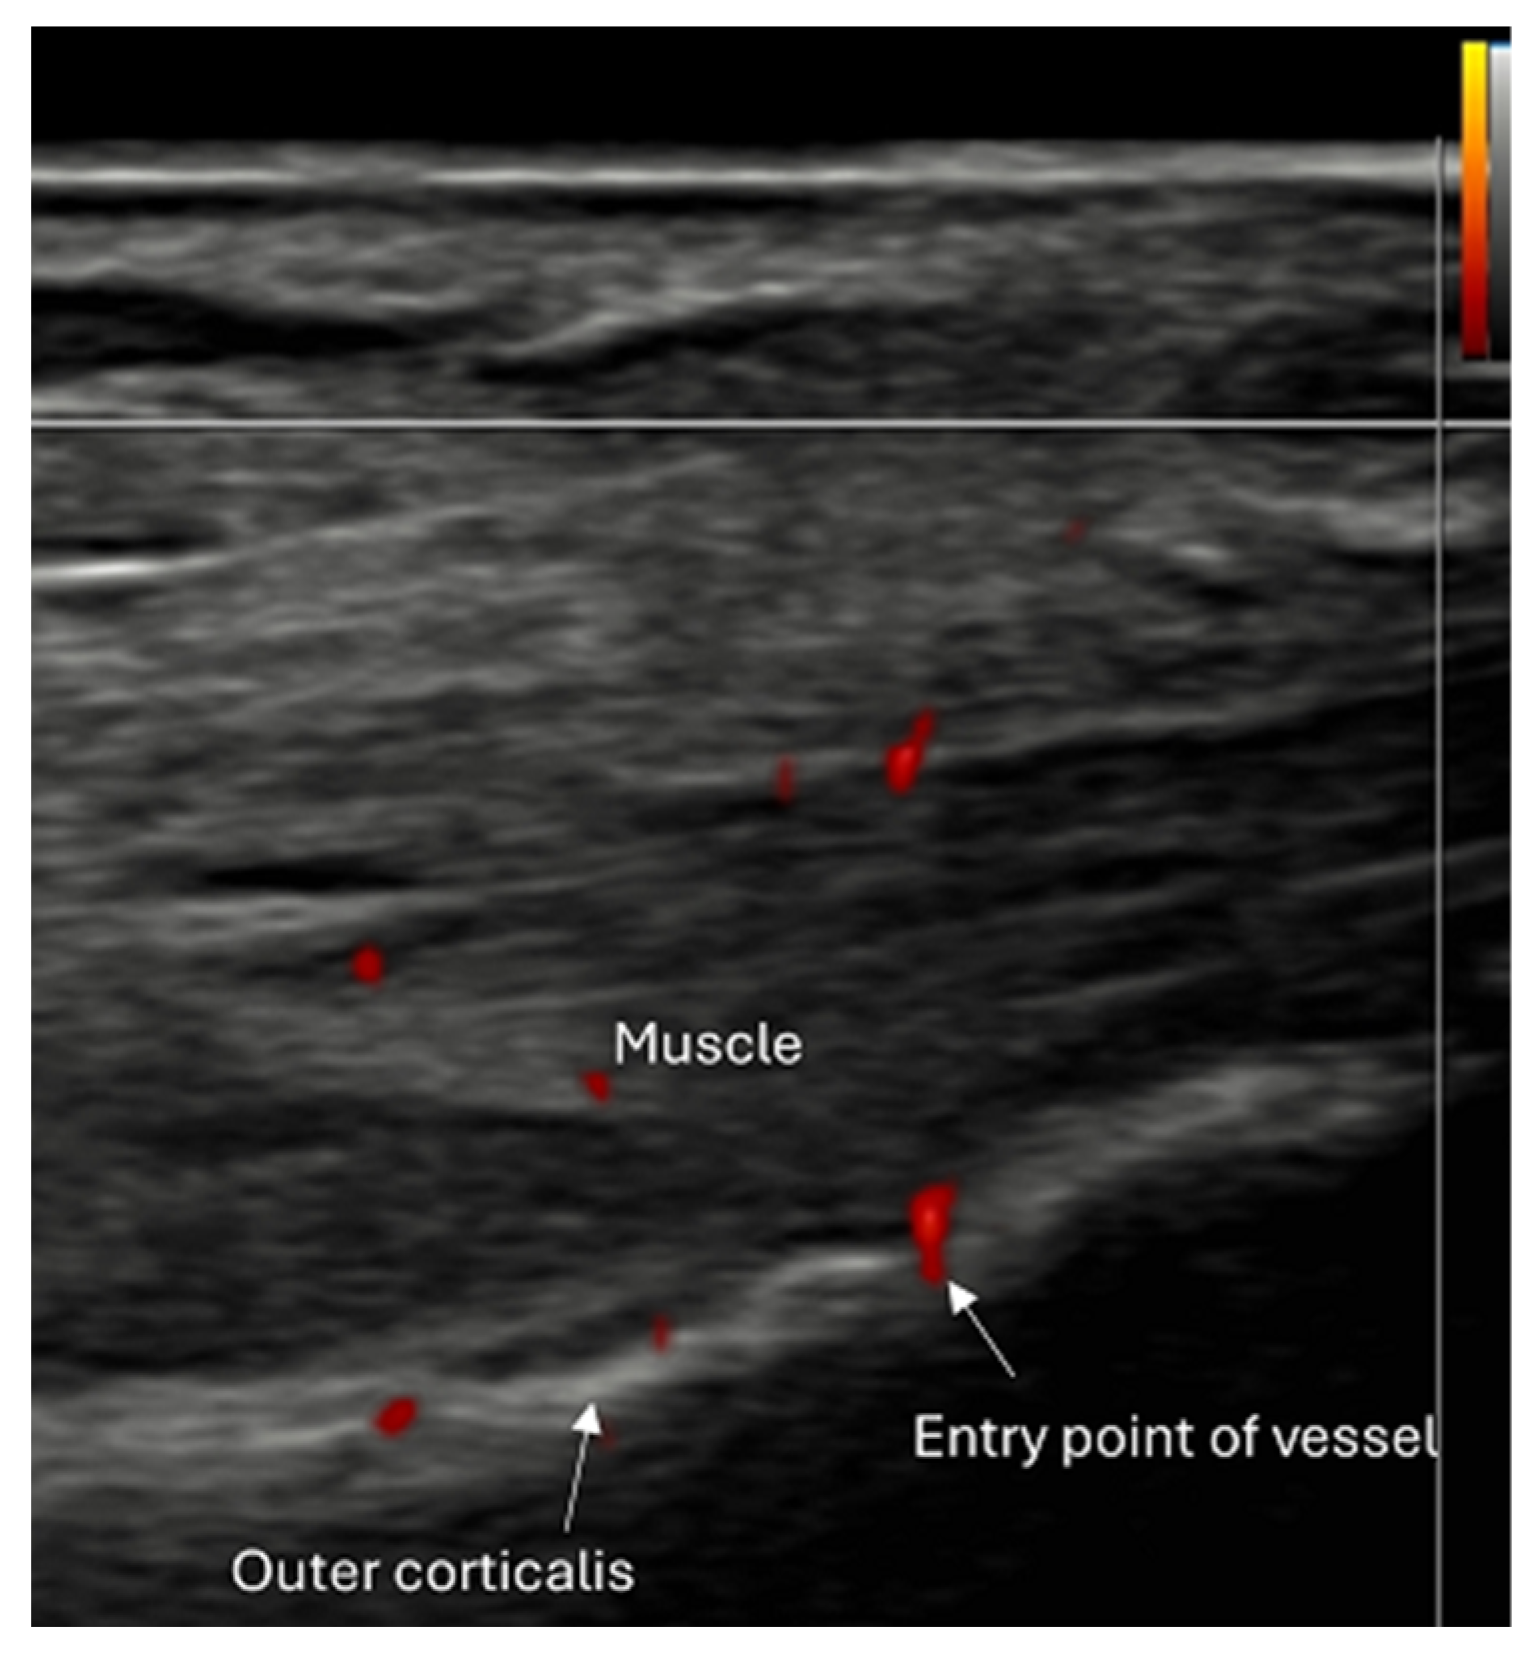

4.2. Sonoanatomy of Fractures [Figure 5, Figure 6, Figure 7 and Figure 8]

- Local hematoma or soft tissue edema: fluid collections or increased echogenicity near the fracture site indicating bleeding and inflammation.

- Periosteal thickening or elevation: the periosteum may appear thickened or lifted due to injury or early callus formation.

- Use of color and power Doppler: When employing Doppler techniques to assess vascularity related to inflammation or healing, care must be taken to avoid excessive probe pressure. Over compression of the tissue can collapse small vessels, leading to false-negative findings.